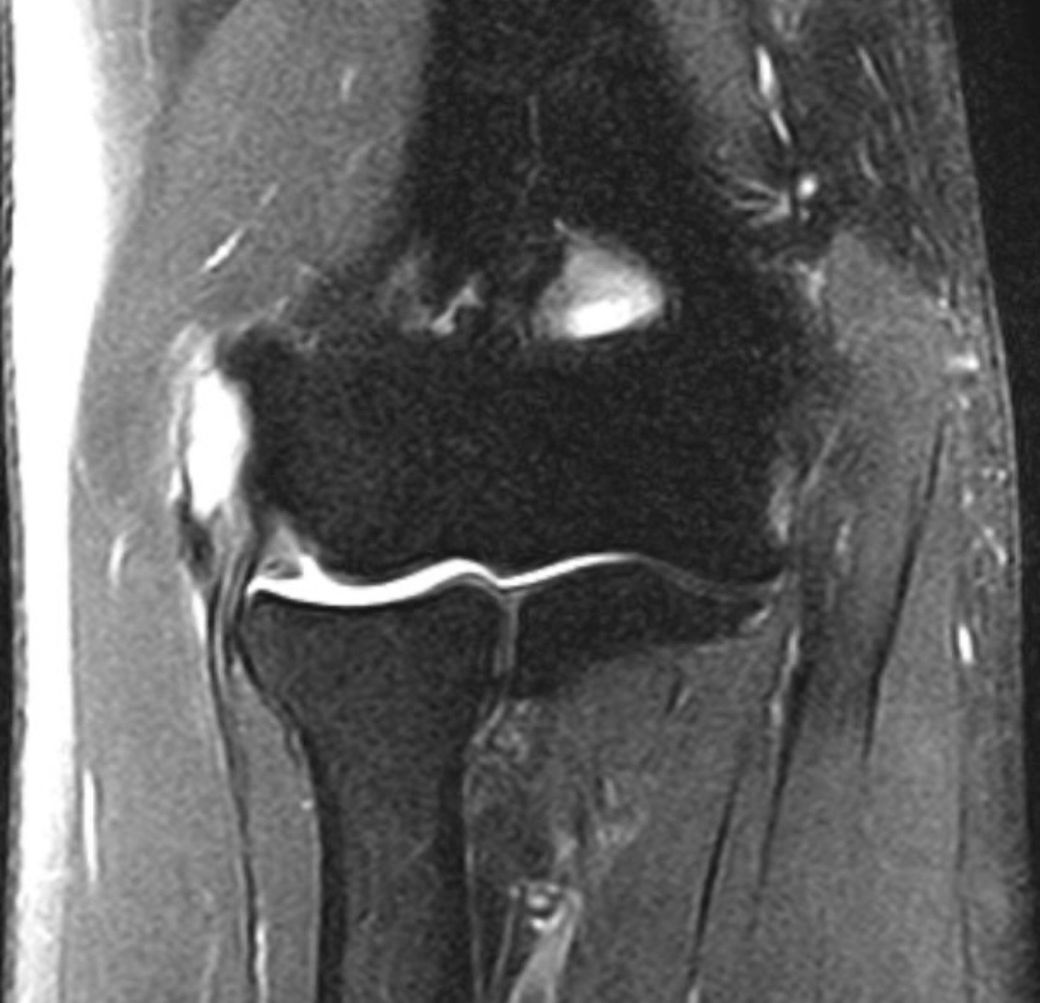

팔꿈치mri인데 수술이 필요한 정도 일까요?

오른쪽 팔꿈치 입니다

• 1번 째 사진

통증이 5년이상 장기적으로 지속되신 경우, MRI는 주치의가 촬영 검사에서 보이는 손상범위를 종합하여 판단하고 보존적인 치료를 지속하셔도 큰 호전이 없는 경우에는 수술을 고려하실 수 있는데요,

올려주신 사진으로는 질문자분의 증상과 이전 자효와 비교하는 등의 종합적으로 판단하기 어렵기 때문에

MRI 사진 한 컷만으로는 알 수 없습니다.